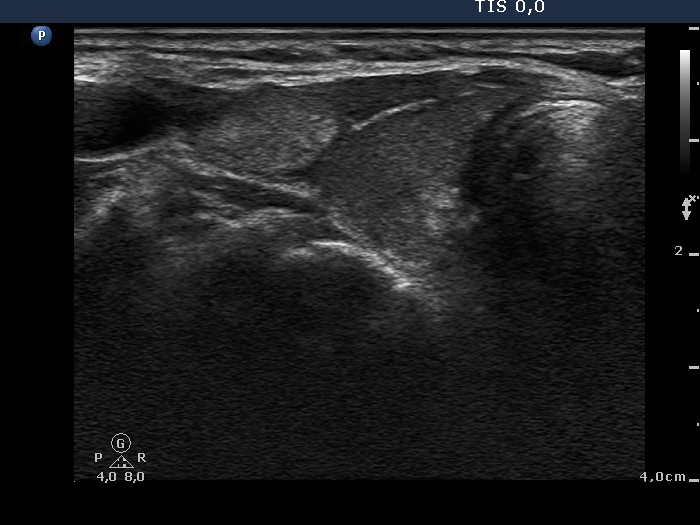

Ultrasonography: the thyroids were moderately hypoechogenic. There was an echonormal, inhomogeneous mass next to the upper pole of the right lobe. Muscle fibers were found between the thyroid and the hyperechogenic lesion. The latter displayed type 2 vascular pattern.